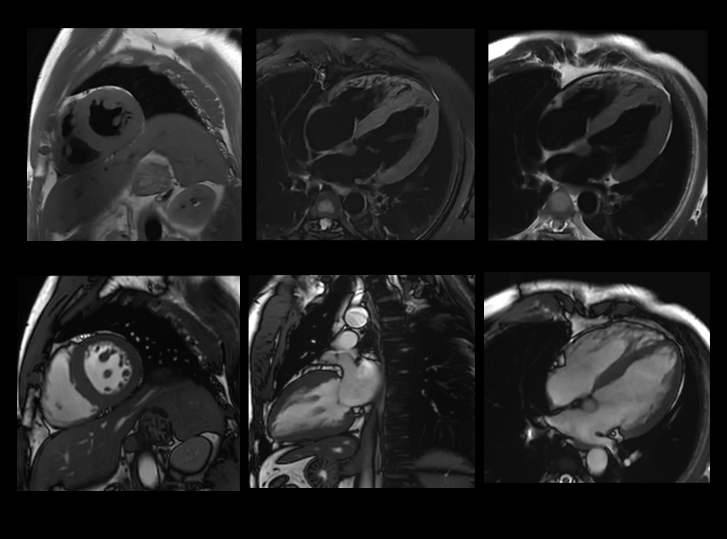

高分辨率心脏成像